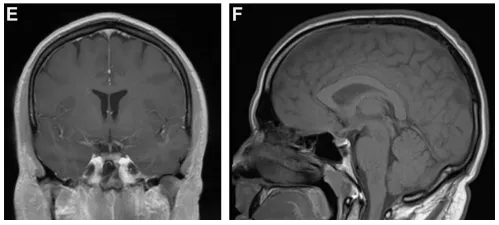

最终患者接受经额颞颞入路肿瘤切除术。术中见肿瘤质地柔软,已压迫右侧视神经。手术实现肿瘤全切(图3),视神经管获得充分减压。术后病理确诊为WHO Ⅱ级脑膜瘤。

图3.(左)矢状位T1加权及(右)轴位T1加权增强MRI显示病变全切除,未见残留病灶。

术后患者头痛显著改善,右眼视力问题消失。术后3个月接受辅助放疗(总剂量5400 cGy/30次),虽出现皮肤反应及疲劳症状,但末次随访(术后5个月)时神经功能完好,未遗留任何后遗症。